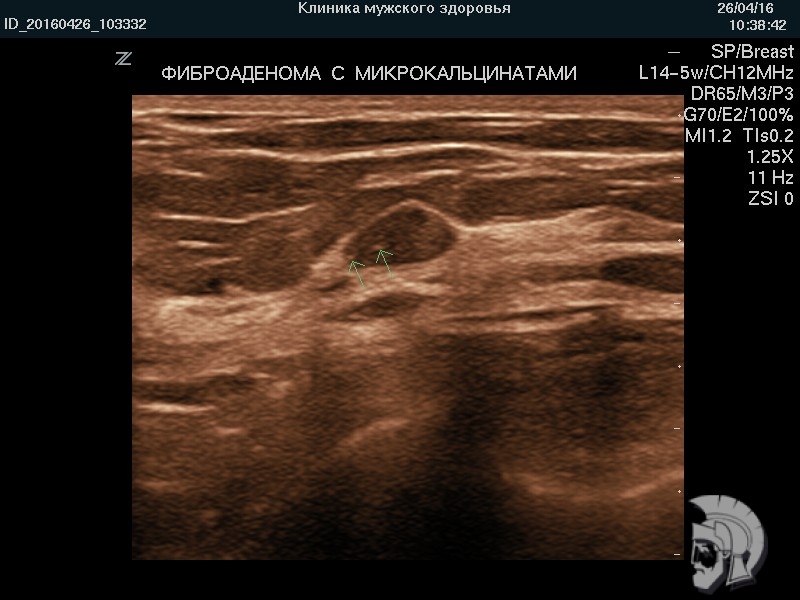

УЗИ груди. Фото фиброаденомы у мужчины 28 лет.

ФИБРОАДЕНОМА с отложениями извести в виде подвижного шарика |